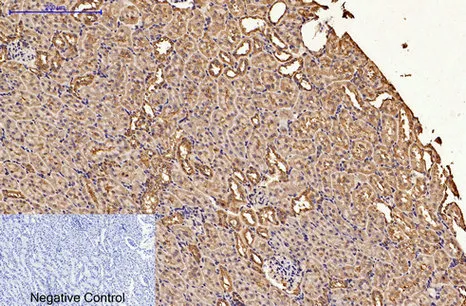

AFP alpha 1 Fetoprotein(17C5)Mouse Monoclonal Antibody

Cat: AMM06666

Size1:50μL Price1:$118

Size2:100μL Price2:$220

Size3:200μL Price3:$380

Application:WB,IHC-P,IF-P,IF-F,ICC/IF

Reactivity:Human

Conjugate:Unconjugated

Optional conjugates: Biotin, FITC (free of charge). See other 26 conjugates.

Gene Name:AFP